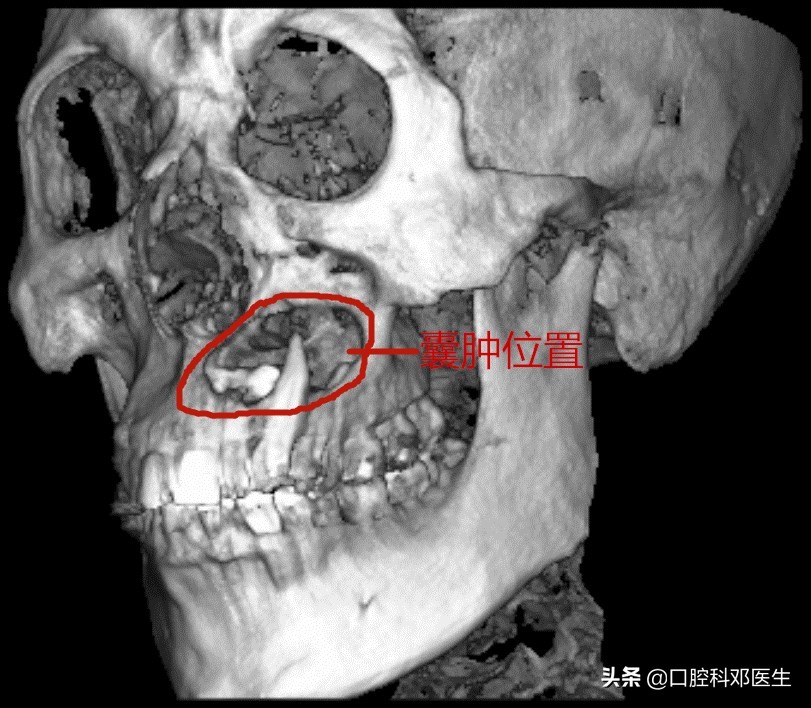

40岁严某最近20天比较苦恼,朋友们都说他脸肿了,平时也不痛不痒的,怎么脸就像吹气球样的越来越肿了呢?而且连张口都困难了。于是他来到长沙市中心医院口腔科检查,一检查牙齿和口腔都没有问题,医生建议他拍个口腔X线片看看,不照不知道,一照吓一跳,X线片显示他的左侧上颌骨已经被吃空了,必须住院进行上颌骨囊肿根治手术。

囊肿波及范围大

接诊的邓医生介绍:这位患者脸肿大是由于左侧上颌骨内一个埋伏多生的牙齿所引起的,由于牙齿无法正常萌出,经过时间的积累,从而诱发囊肿,囊肿一般都不痛不痒,越长越大,像鼓气球一样,逐渐破坏了周围的骨头,如破坏上颌骨前壁,就会突破至软组织,引起脸部肿大;如破坏牙槽骨,则会导致牙齿松动移位,引起牙根吸收疼痛等症状。